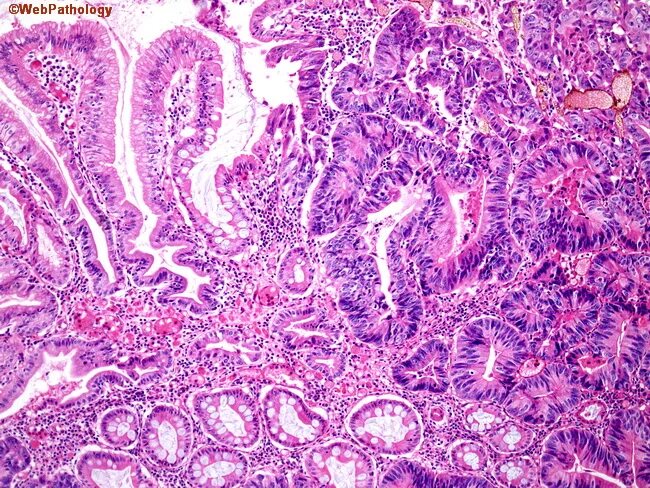

Полип желудка гистология